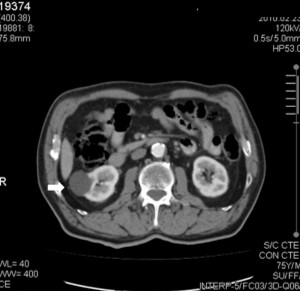

La Categoría I define la lesión como densidad agua (0-20 UH), sin septos o calcificaciones, ausencia de polos sólidos y sin realce a la administración de medio de contraste yodado IV.(19, 20) Su clasificación sería de quiste simple benigno y no requeriría ningún tipo de evaluación posterior. Son lesiones asintomáticas que rara vez requieren tratamiento. No es necesario realizar controles posteriores (Anexos 3 y 4).

La Categoría II define una lesión con septos finos lisos (< 1mm), calcificaciones lineales continuas o discontinuas o lesiones densas homogéneas en la pared o tabique pero que no experimentan realce a la administración de medios de contraste yodado IV en TC o paramagnéticos en RMI. Su clasificación es de lesión benigna (proteáceos, hemorrágicos, infecciosos).(19, 20) Estos quistes son hiperdensos (40-90 UH < 3cm), mínimamente complicados y no precisan cirugía, deben ser controlados (Anexos 5 y 6).